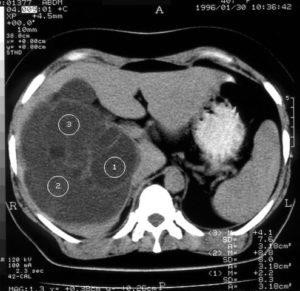

Нажмите чтобы увеличить.

Самый популярные способ диагностики кисты печени – это ультразвуковое исследование (УЗИ). С помощью УЗИ печени и брюшной полости определяется состояние органа, определяется размер образования, количество, в случае множественного поражения. Для исследования природы кисты проводится пунция (биопсия). Таким способом исследуют содержимое жидкости кисты. Для диагностики кисты используют также компьютерную томография (КТ) и магнитно-резонансную томографию (МРТ).